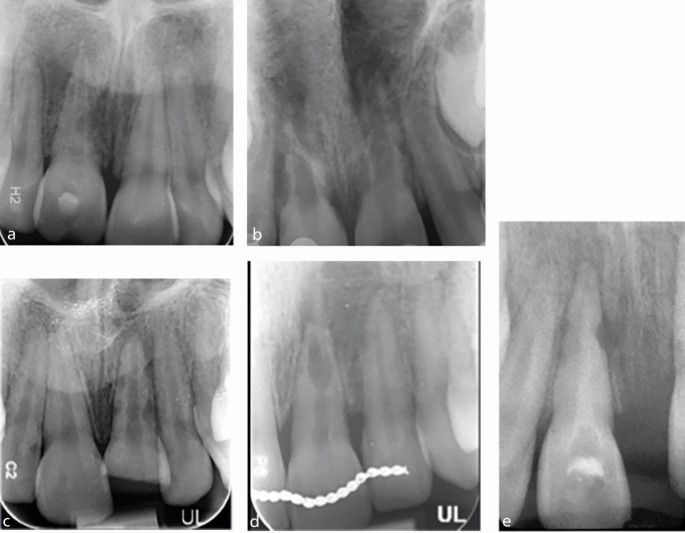

Root resorption is defined as the loss of dental hard tissue as a result of osteoclastic cell action.34 Several types of root resorption can occur following TDIs, including infection-related resorption, replacement-related resorption, cervical root resorption and surface resorption. Root resorption is being increasingly diagnosed by clinicians, most likely due to improved access to advanced means of diagnosis, such as CBCT, which is more likely to detect resorption than plain film radiographs.35,36 CBCT provides a comprehensive 3D evaluation of the site and is consistently useful for guiding a surgical approach and minimising iatrogenic damage, as well as identifying resorption. The most common type of root resorption following TDI is infection-related, followed by replacement-related.37 Infection-related resorption presents radiographically as a radiolucent lesion/s, whereas replacement resorption will present a more radio-opaque appearance where bony infill is apparent in resorptive defects and in direct contact with the root surface (Fig. 1).

Resorption can occur on the internal and external aspects of the root surface (Table 2). In infection-related resorption, damage to the protective superficial layer of cementum or predentine must occur in the presence of bacteria.38 Once it starts, the resorptive process will progress for as long as the root canal remains infected, which can result in loss of the whole root and subsequently tooth loss, and this can be rapid in children. Importantly, appropriate endodontic treatment to remove the necrotic pulp and to achieve a root canal rendered free from the presence of bacteria (by dressing with non-setting calcium hydroxide) can arrest the progression of the infection-related root resorption.28

If less than 20% of the tooth surface is involved, the ankylosis may only be a transient; however, if it is more established, there is no effective treatment.41 In a growing child, this situation leads to infraocclusion of the affected tooth, and arrest of vertical growth height of the alveolar ridge leading to an alveolar defect that may be difficult to restore prosthetically (Fig. 2). Children may present with tilting of the adjacent teeth due to continued growth and development of the adjacent teeth and alveolus compared to the ankylosed tooth and its related alveolus. This is a particular risk from the age of ten years until completion of the early teenage growth spurt. These cases should be referred for urgent specialist management. Management options are limited and often involve decoronation (to preserve the alveolar bone until adulthood when advanced restorative options can be considered) or tooth loss (extraction may be destructive and leave a residual vertical bony defect) (Fig. 3).

Management of immature teeth following a TDI

Recovery and healing of the pulp (revascularisation) is more likely in immature teeth with open apices. Pulp necrosis in immature permanent teeth can result in cessation of root development with a resultant weakened root, apical inflammation, inflammatory root resorption, and apical bone loss. Immature roots are fragile and susceptible to root fracture, even to mild forces in the future. Recent developments and research in paediatric dentistry and endodontics have aimed to progress the potential of regenerative endodontic procedures.50,51,52 There is much to learn about the nature of the vital tissues that might be regenerated, the optimal tissue scaffold that might be required, and the ideal disinfection strategy to support success. It is largely agreed that regenerative endodontic procedures may develop to offer an improved prognosis where there has been careful case selection of immature traumatised teeth. Such cases include patients aged 7-9 years, when the root walls may be especially thin and susceptible to fracture, even in the presence of apical root end closure procedures with hydraulic calcium silicate cements (Fig. 4).53 The management of the child who has experienced complex dental trauma is often best guided by a specialist in paediatric dentistry, with the primary dental care practitioner providing invaluable support.